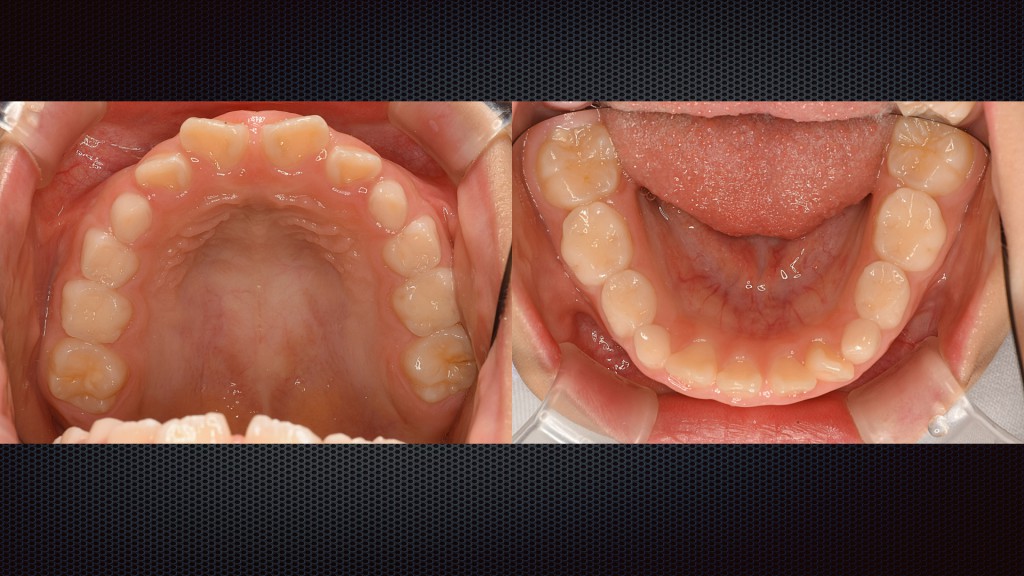

⇧左の写真は治療前になり、過去に治療した詰め物が不適合になり表面から齲蝕になっています。右の写真が治療後で歯肉の改善も認められます。ここからちゃんと維持するためにも日々のブラッシングが大切です。虫歯のリスクを軽減するためにも定期的な検診をオススメします。